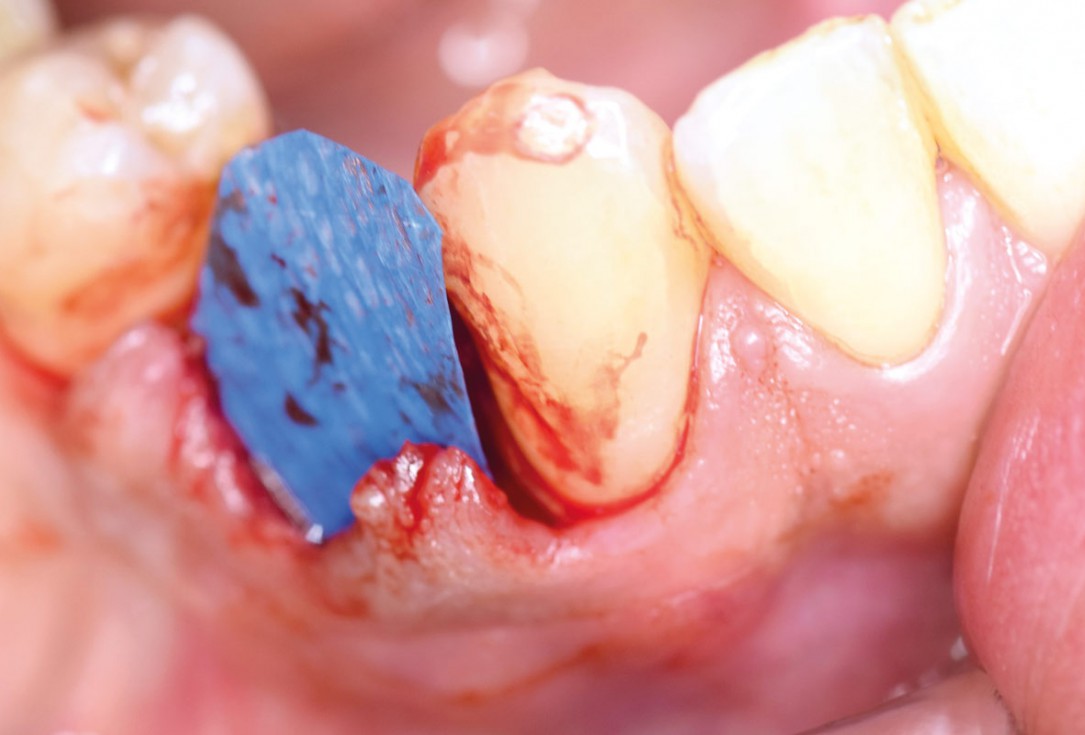

Initial clinical situation: 9 mm pocket depth associated with root fracture